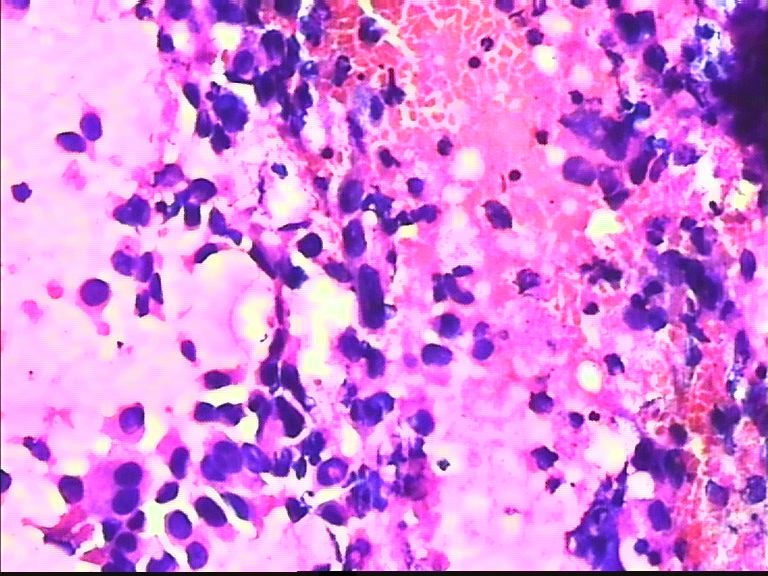

38岁 乳腺肿瘤 女

• 38岁 乳腺肿瘤 女图3

图3

考虑癌:图18细胞核形式不规则,染色质粗块状,可见核仁.

乳腺癌

乳腺癌。

浸润导管癌

好像重复了。浸润性导管 癌。

从所给图看恶性是没什么问题!染色有点过,染色质结构欠清晰;关于细胞学判断浸润的问题我想应综合来判断,如单个细胞的异形性,细胞整体弥散情况,细胞微粒结构以及间质成分等等,个人的认识也起到一定因素,细针穿刺中最常规用的还是--导管癌。